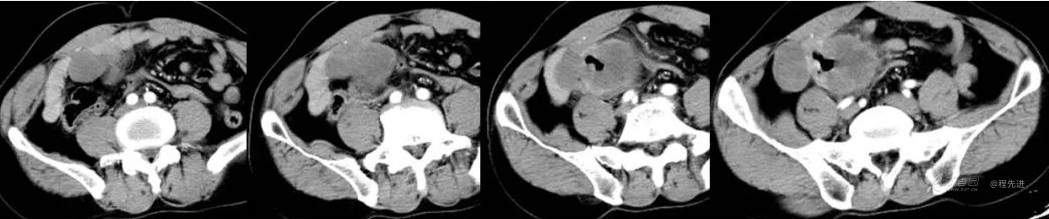

门静脉期